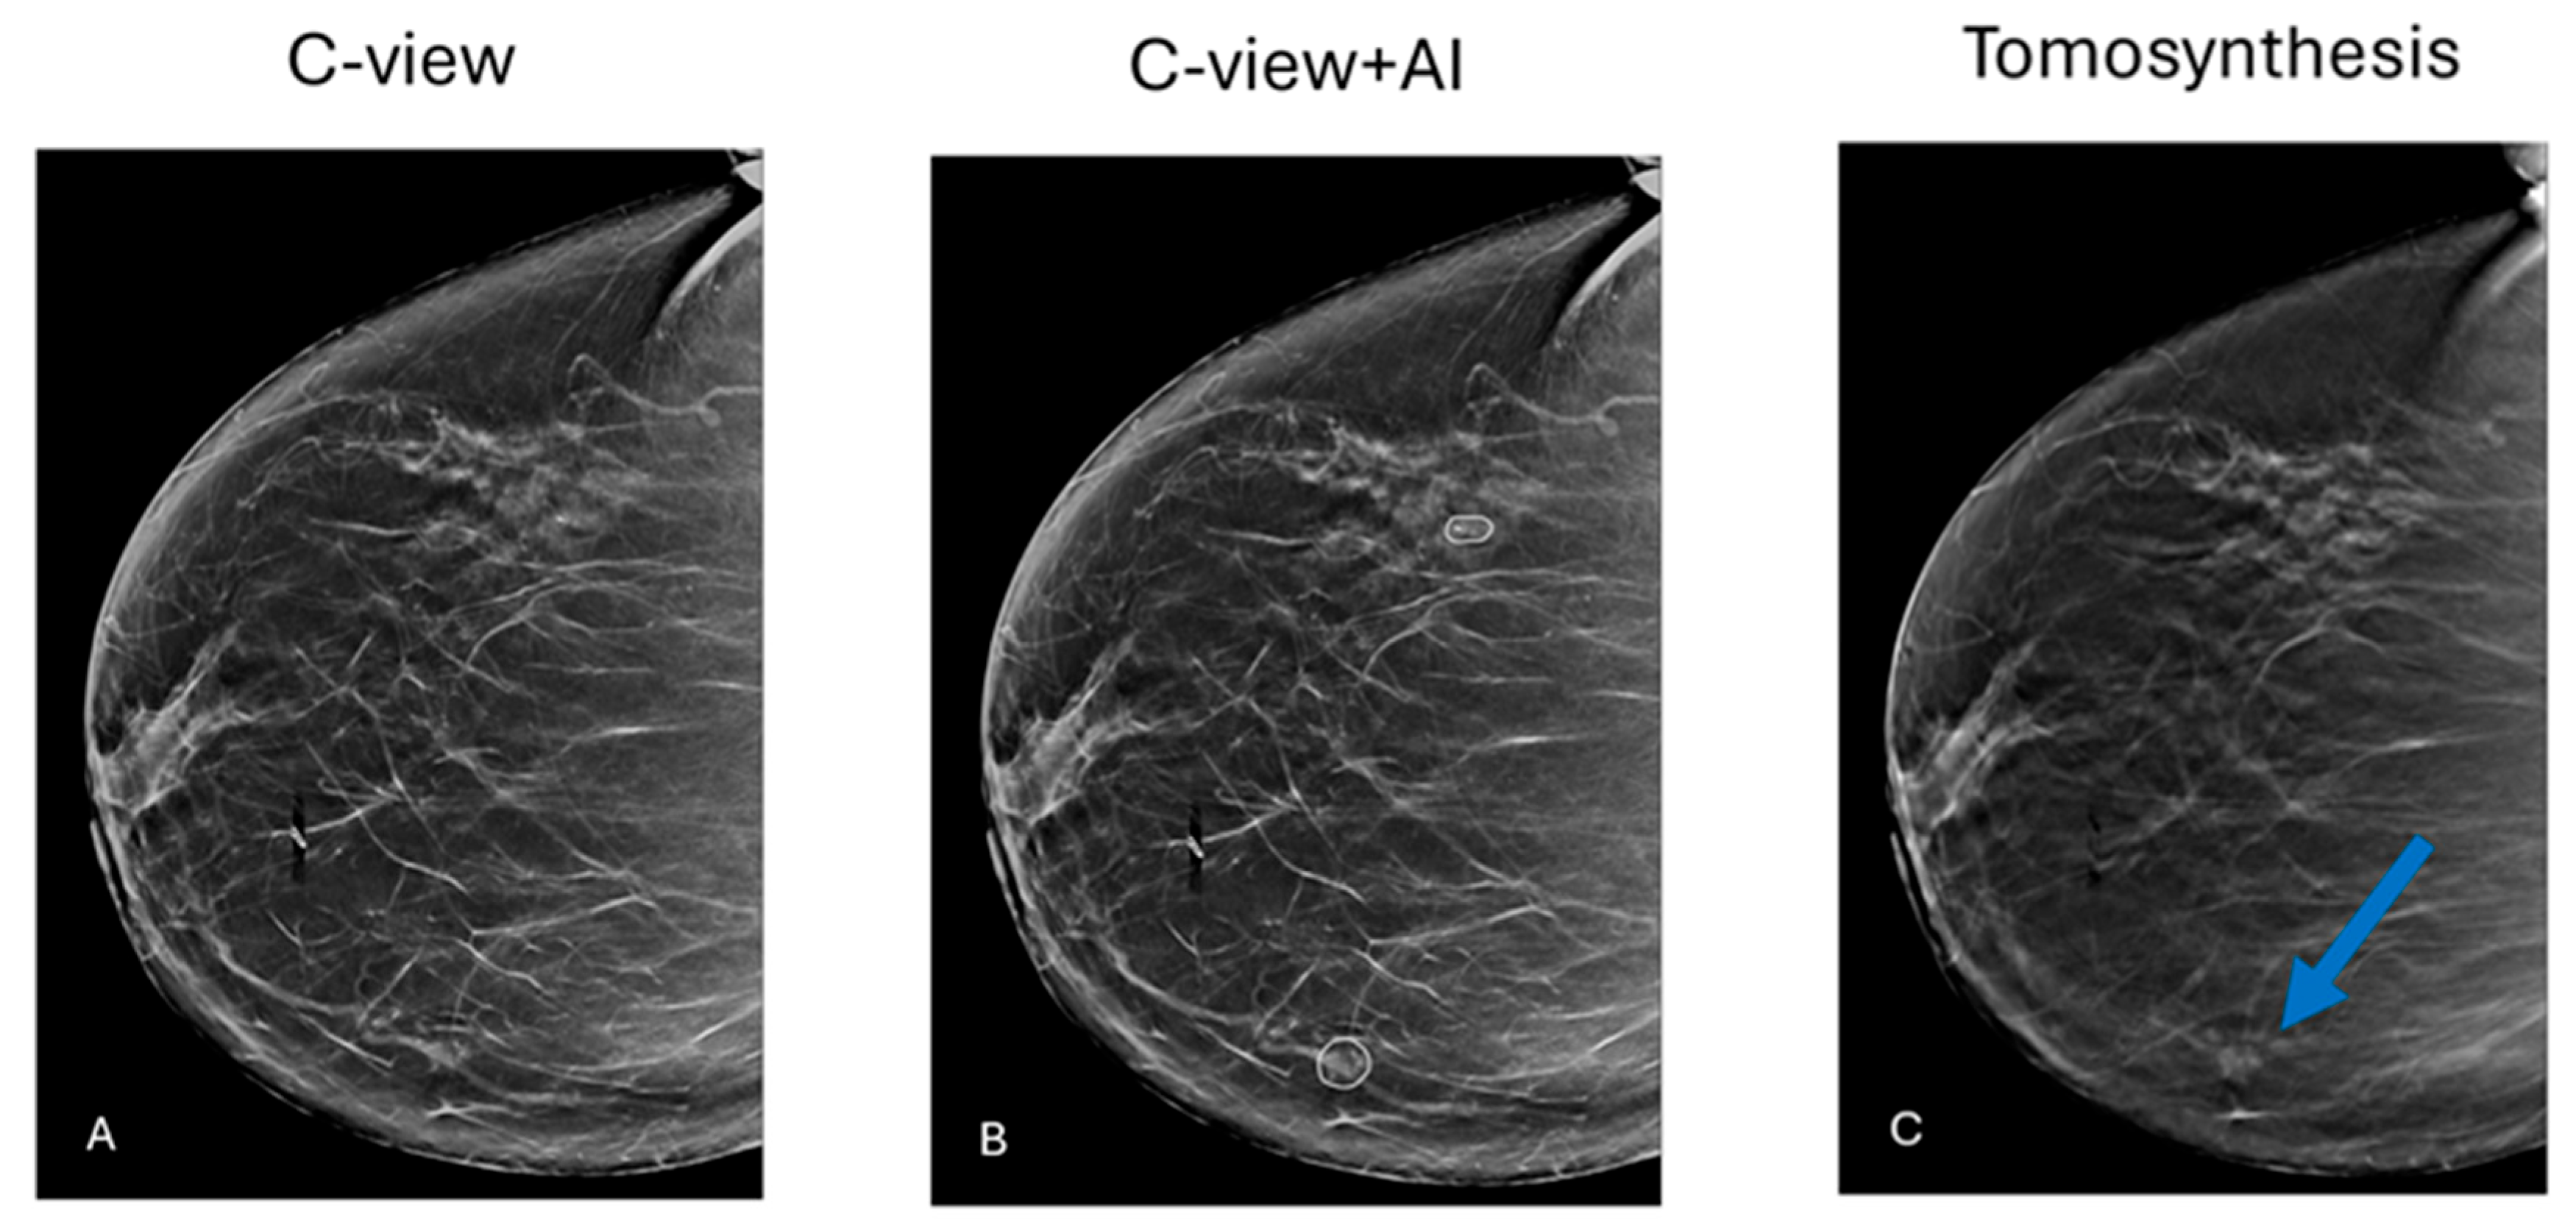

2.1. Software System

2.2. Reading Protocols